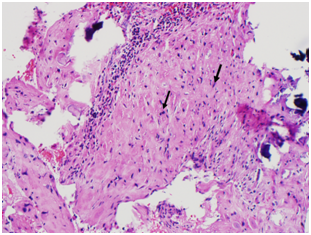

The CSD resection specimen was sent for pathologic examination which showed fragments of endomyometrial tissue with scarring consistent with the cesarean scar, along with old placental side nodule with dystrophic calcifications (Figure 6) (Figure 7).

Figure 7 Patient 2, Pathology slides: a. The pathology figure 7a would roughly correspond to the red circle in figure 6: Low power view of resected fibrotic cesarean scar (white arrow) with placental site nodule (black arrow). (H&E stain) b. High Power view of placental site nodule (black arrow) showing hyalinization with degenerative implantation site trophoblast. (H&E stain).